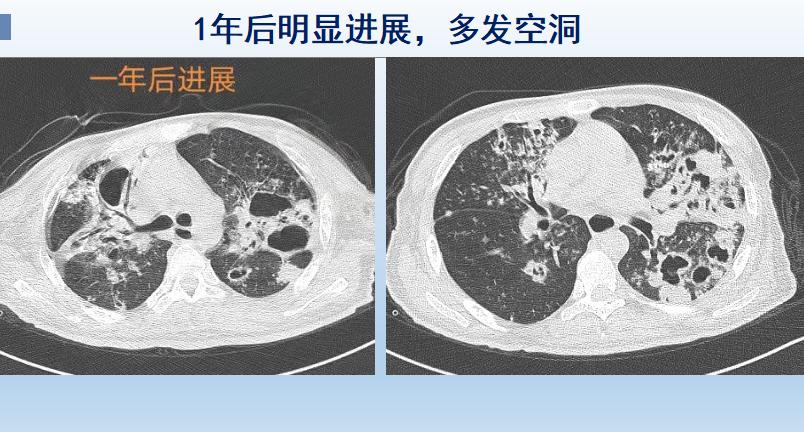

一年后,结核杆菌基本统治了他的双侧肺脏,以他的肺叶为食,繁育出一波又一波新的结核杆菌后代,并吃出了大量的空洞,还有广泛的支气管损伤:

这回症状严重多了,小伙子出现反复发热、剧烈咳嗽、经常咳血、夜间入睡困难,明显消瘦……

到这个程度就有生命危险了,重症感染、呼吸衰竭、血管破溃大出血都可以夺去他的生命,而且治疗已经非常困难了。